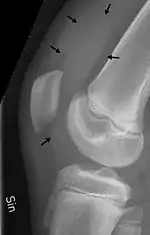

| Traumatic effusion of the right knee, with swelling lateral to the kneecap marked by an arrow | |

An X-ray is useful to verify that there is no break or dislocation when there is a history of trauma. May show signs of osteoarthritis.